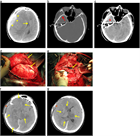

急性硬膜下血腫

1. 頭部外傷受傷直後から片麻痺等の神経症状や意識障害が持続する場合には、急性硬膜下血腫の存在を想起し呼吸・循環管理を行いつつ速やかに頭部CT撮影を行い診断する。

1. 抗血栓薬内服中の高齢者では軽微な外傷でも受傷することがあり、急速な意識障害の進行や亜急性の経過をとることもあり注意を要する。